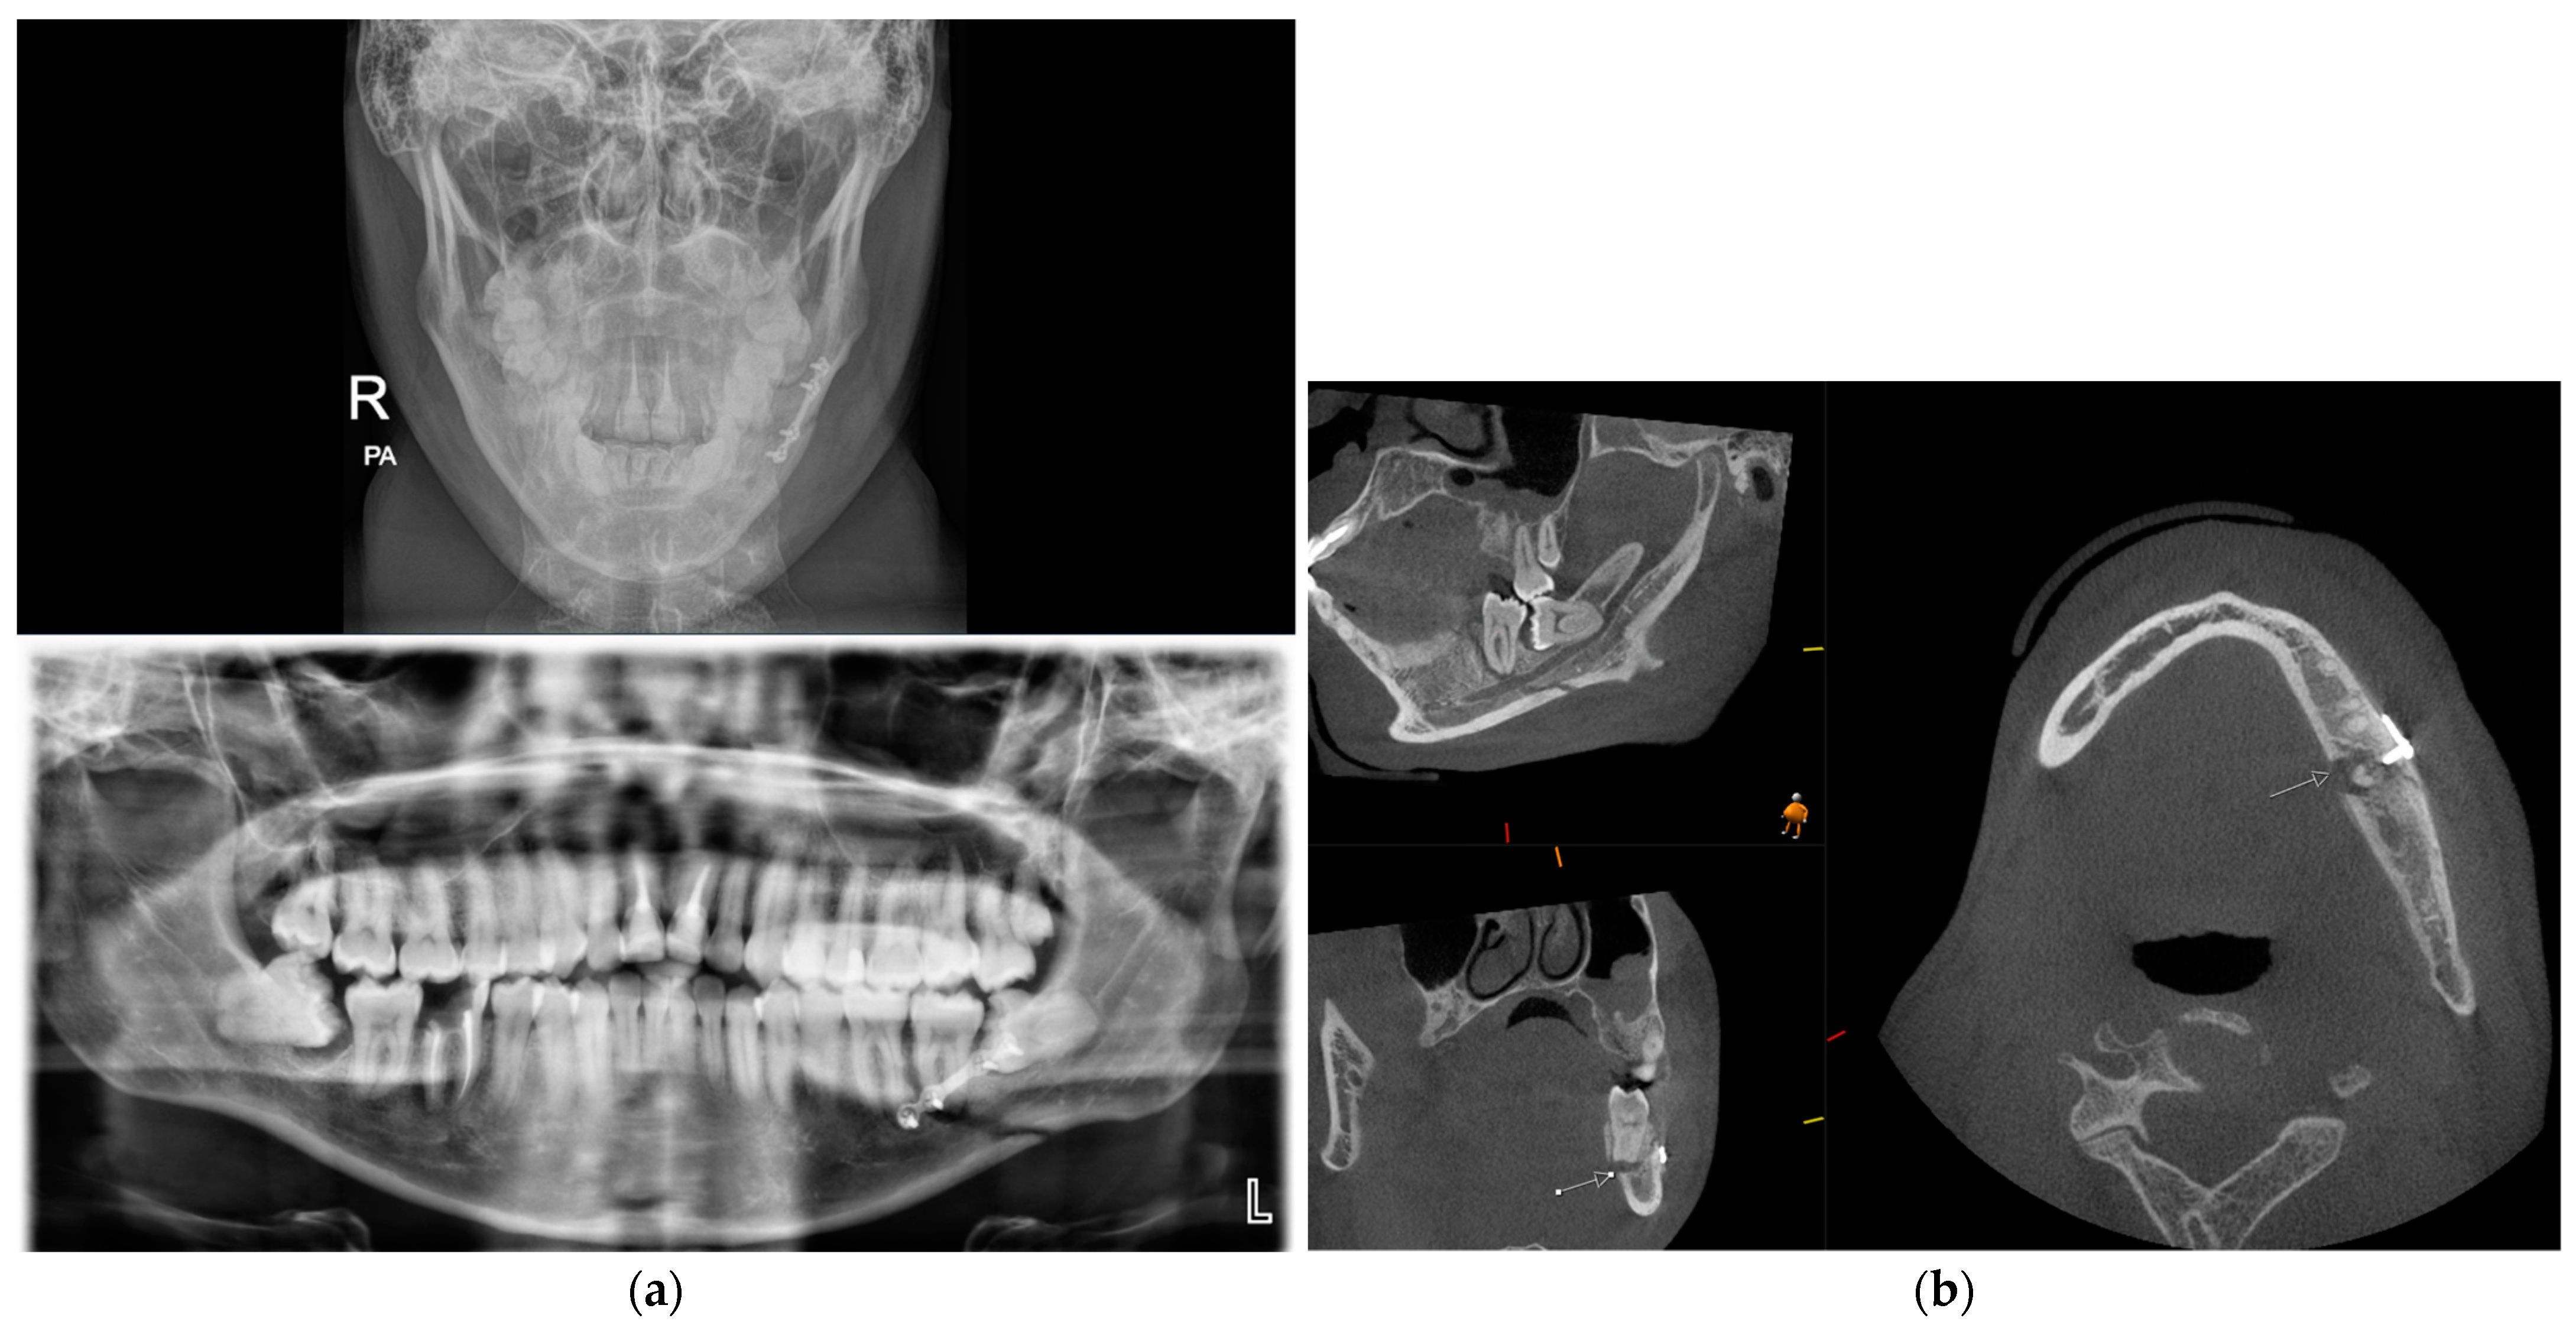

3.3. Cone Beam CT for Assessment of Frontal Sinus Fractures

3.6. Cone Beam CT for Assessment Fractures of the Zygomatic Maxillary Complex and Midface

- Shintaku, W.H.; Venturin, J.S.; Azevedo, B.; Noujeim, M. Applications of cone-beam computed tomography in fractures of the maxillofacial complex. Dent. Traumatol. 2009, 25, 358–366. [Google Scholar] [CrossRef] [PubMed]